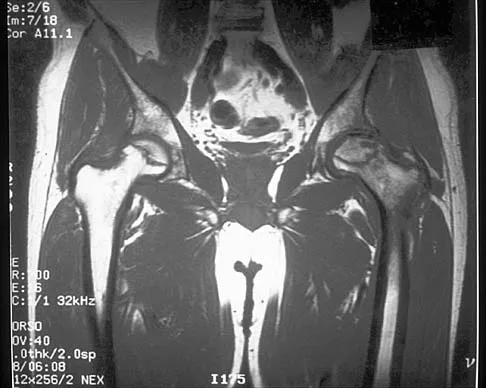

Question 15

Figure 30 shows the MRI scan of a 68-year-old woman who has left hip pain. What is the most appropriate treatment?

Explanation